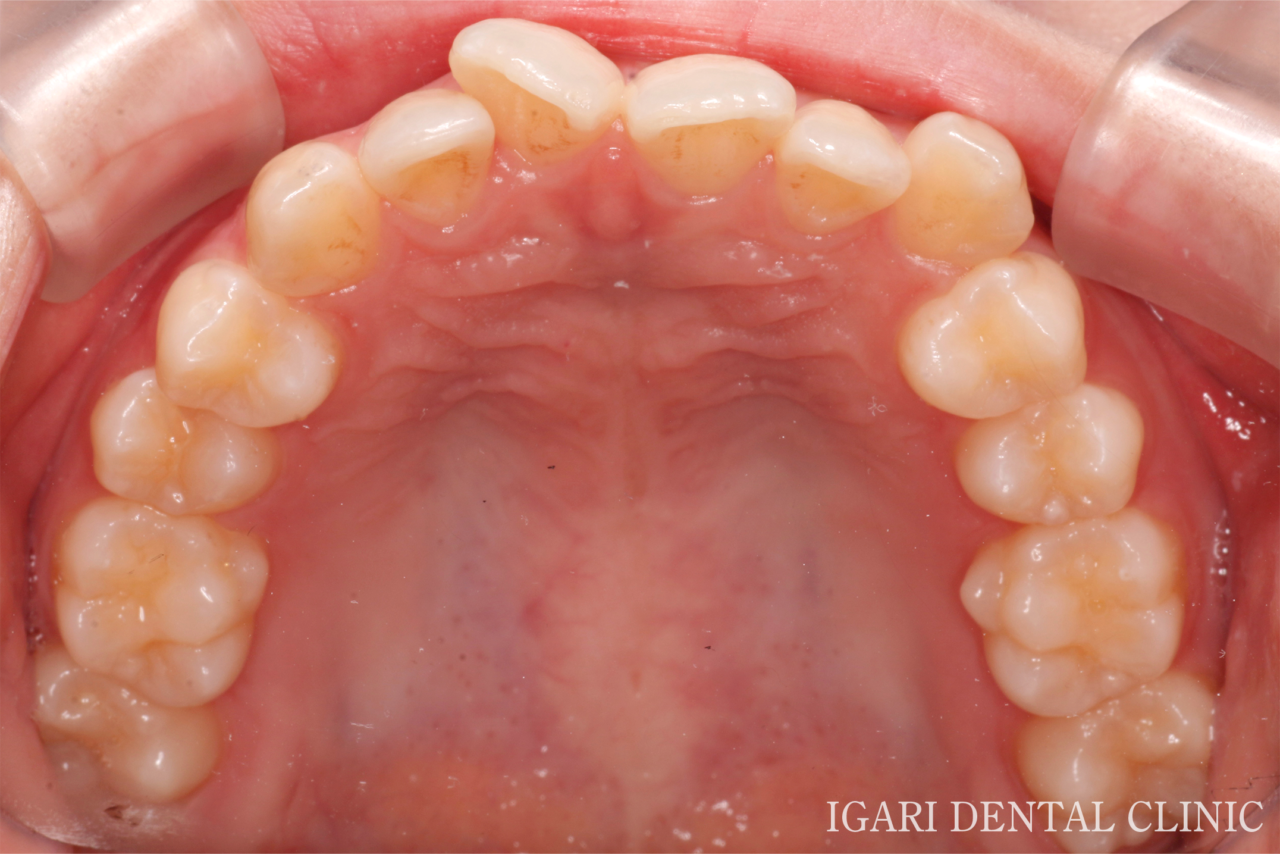

治療前上顎

真ん中右上の歯がねじれながら傾いて生えており(翼状捻転)、上下の前歯に重なり(叢生)がみられました。

また、左側の犬歯が低い位置にあり、いわゆる八重歯の状態でした。 -